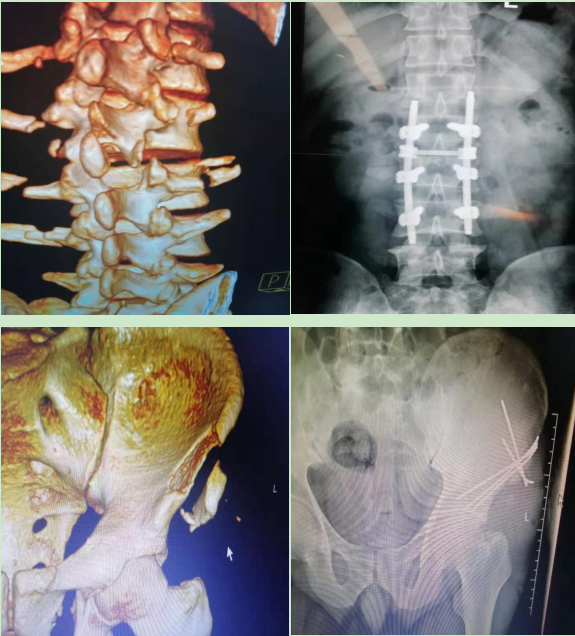

脊柱骨折手术多数为四级手术,脊柱骨科约占住院手术量的3%,包括胸腰椎压缩骨折切开复位钉棒内固定术;椎间盘突出髓核摘除术;骨盆切开复位内固定术;髋臼骨折切开复位内固定术等。